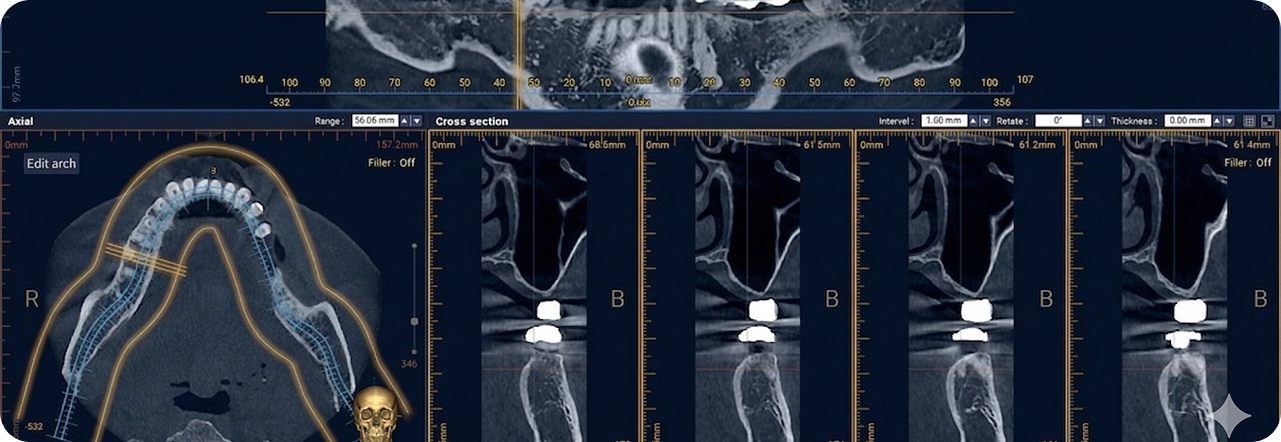

다양한 디지털 진단 장비를 활용

오차 줄인 안전한 진료

성공적인 임플란트 식립을 위해서는 정밀한 진단이 필수적입니다.

3D-CT, 구강 스캐너 등 다양한 디지털 장비를 이용하여

치아, 잇몸뼈, 신경 위치 등을 정확하게 파악해 수술 오차를 최소화하고,

통증 및 출혈을 줄여 더욱 안전하고 편안한 임플란트 식립이 가능합니다.

3D-CT를 통한 정밀 진단

3D-CT 분석을 통해 상악동 구조와

골 상태를 정확하게 진단합니다.